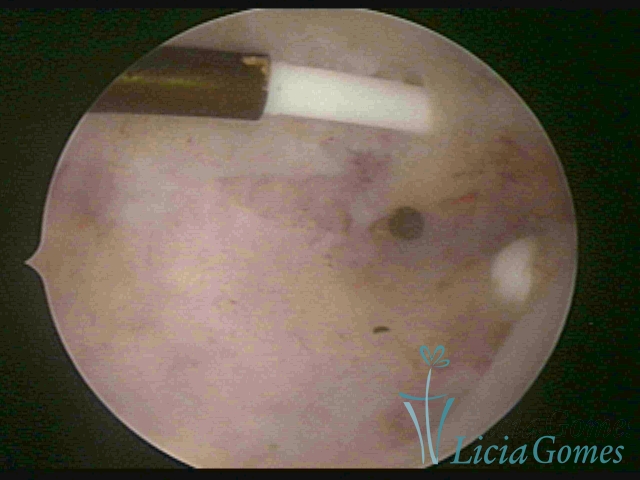

Canal cervical com fio do DIU